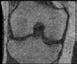

Abb. 5 a + b: Hochaufgelöstes Bild des Hippocampus; 0,15 mm x 0,15 mm; 2 mm Schichtdicke; rechts mit AiCE-Rekonstruktion. Mit freundlicher Genehmigung des Unversitätsklinikums Bordeaux. Abb. 6 a + b: Hochaufgelöstes Bild des Knies; 0,15 mm x 0,15 mm (interpoliert); 1 mm Schichtdicke; rechts mit AiCE-Rekonstruktion.

42 // VISIONS 31

spielsweise einen Knorpelschaden im Knie im Detail zu zeigen.